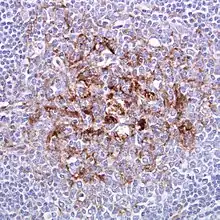

| Biopsy of the tonsil in variant CJD. Prion protein immunostaining. | |